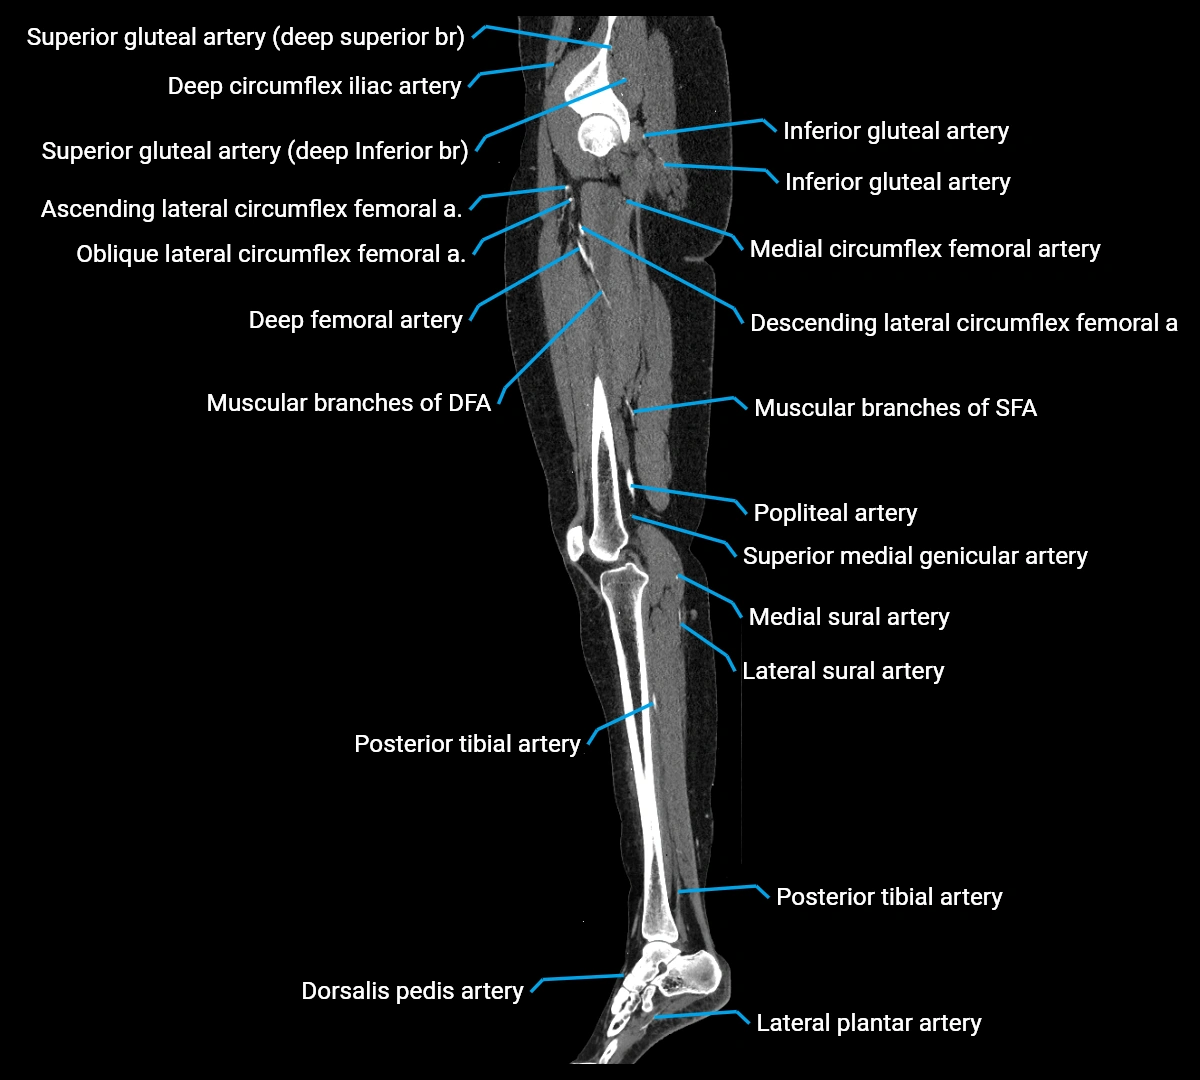

CT images

image